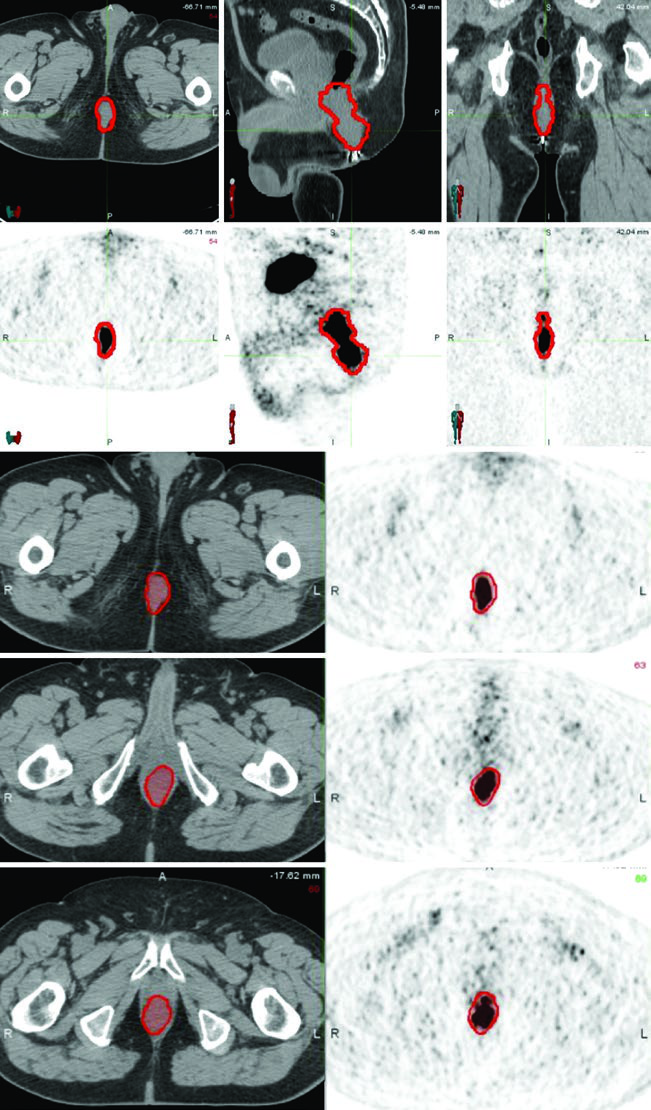

O PET/CT é recomendado tanto para estadiamento quanto para planejamento do tratamento, auxiliando na delimitação da doença macroscópica. Contudo, áreas de baixa captação no PET não devem substituir achados do exame físico ou anormalidades detectadas na CT ou RM. A integração multimodal de imagens é a abordagem mais segura.

A CT de simulação com contraste intravenoso e espessura de corte ≤3 mm permite delinear os vasos sanguíneos pélvicos e o volume tumoral macroscópico. Quando disponível, fusão com PET/CT ou RM auxilia significativamente na definição dos volumes-alvo.

| GTV-P, GTV-N | GTV-P: toda doença macroscópica ao exame físico e imagem. GTV-N: linfonodos ≥1,5 cm, PET-positivos e/ou comprovados por biópsia. Distinguir GTV-Na (≤3 cm) de GTV-Nb (>3 cm) |

O caso T2N0 demonstra quimorradioterapia definitiva com IMRT: PTV-LR e PTV-HR tratados simultaneamente a 40 Gy (1,6 Gy/fração) e 45 Gy (1,8 Gy/fração) em 25 frações, respectivamente. Depois, o PTV-P recebeu boost sequencial a 50,4 Gy (1,8 Gy/fração) em 28 frações totais.

No caso T3N1a com envolvimento inguinal bilateral, PTV-LR e PTV-HR foram tratados simultaneamente a 40 Gy e 45 Gy em 25 frações. Os linfonodos inguinais e ilíacos externos bilaterais foram incluídos no CTV-HR por causa do envolvimento bilateral. Depois, PTV-P e PTV-N receberam boost a 54 Gy em 30 frações totais.